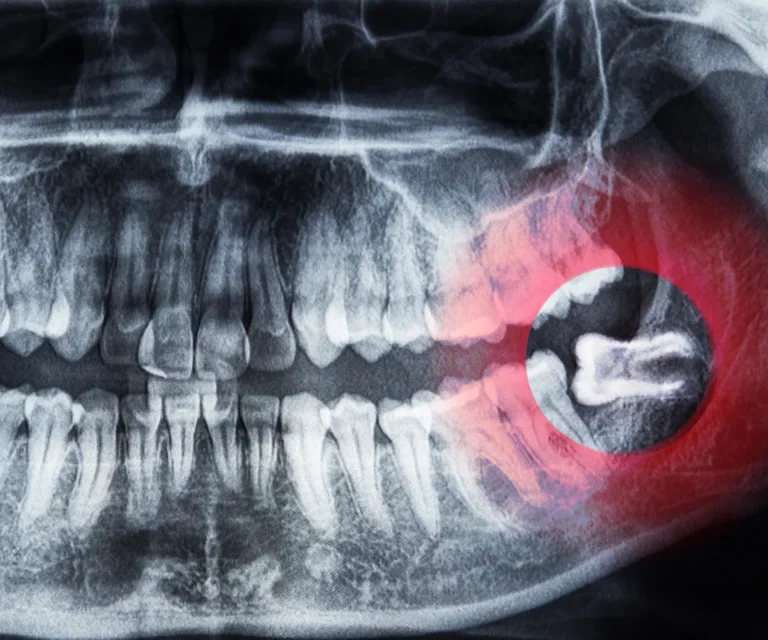

Wisdom Tooth Infection Emergencies

Wisdom teeth are especially prone to infection due to their position in the back of your mouth, making them harder to clean. Common signs of a wisdom tooth infection include:

Our emergency dentists in Tucker can assess whether you need antibiotics, drainage, or immediate extraction to eliminate infection and pain.

A quick but thorough exam, including X-rays if necessary.